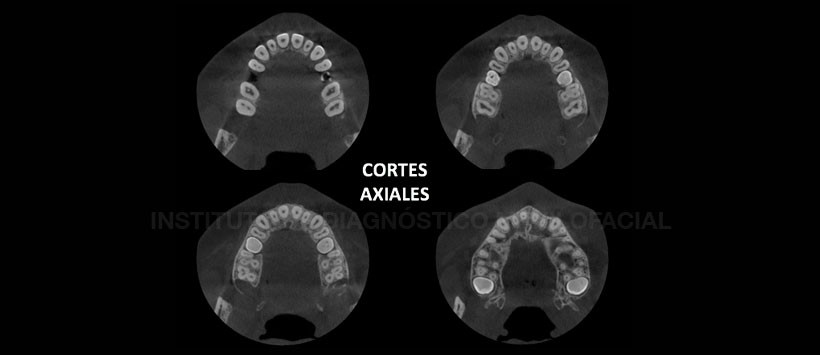

A la evaluación de la tomografía volumétrica (CBCT) en cortes axiales (Figura 2), coronales (Figura 3), transaxiales (Figura 4 y 5) y tangenciales (Figura 6), se evidencia piezas 5.5 y 6.5 en infraoclusión por debajo del límite amelo-cementario de piezas adyacentes, con la corona orientada levemente hacia la tabla ósea palatina el cual que se encuentra erosionada a ese nivel. Se evidencia ausencia del espacio periodontal a nivel radicular  y no se aprecia raíz disto-vestibular de pieza 5.5. Se corrobora la ausencia de los gérmenes dentarios de las piezas 1.5 y 2.5 y por último se aprecia una leve disminución de la longitud de la arcada dentaria superior ocasionado por las piezas 1.6 y 2.6, que se encuentran en posición mesioangular.